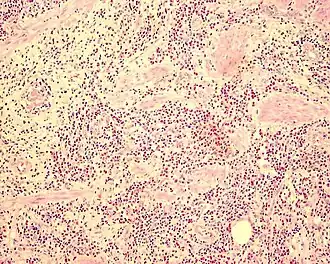

Biópsia revelando Gastroenterite eosinofílica.

Diagnóstico definitivo envolve evidência histológica de infiltração eosinofílica na biópsia. Eventualmente biópsia laparoscópica transmural pode ser necessária.